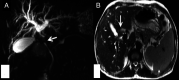

Isolated gallbladder tuberculosis is a rare entity, even in endemic zones. Preoperative diagnosis is usually not possible, with most of the cases being diagnosed either as cholecystitis or malignancy. Histopathological examination of the resected specimen clinches the diagnosis. We present a middle-aged man with obstructive jaundice who was diagnosed to have gallbladder malignancy clinically and radiologically and on microscopy, and was diagnosed as gallbladder tuberculosis with the involvement of the common bile duct.